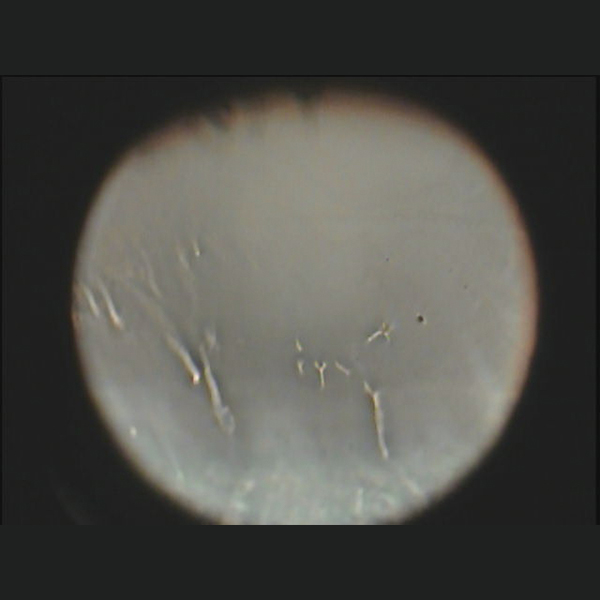

Die Lipidschicht ist eine dünne, etwa 100 nm dicke Schicht.

Aufgrund unterschiedlicher Schichtdicken entsteht ein Interferenzmuster, wenn weißes Licht, das an der Oberfläche der Lipidschicht reflektiert wird mit Licht, das an der Grenzfläche zur wässrigen Schicht reflektiert wird, interferiert.

Ein hochentwickeltes, optisches System, das speziell für die Hornhautform konzipiert ist, macht es möglich die Interferenzen auf einer großen Fläche zu beobachten.

The lipid layer is a thin layer about 100nm thick.

The different layer thicknesses create an interference pattern when white light reflected at the surface of the lipid layer interferes with light reflected at the interface with the aqueous layer.

A sophisticated optical system specially designed for the corneal shape makes it possible to observe interferences over a large area.